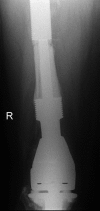

Custom-made endoprostheses can be linked to existing well-fixed implants in the treatment of complex periprosthetic femoral fractures. By adopting this salvage approach, secure implants can be retained in favour of patients undergoing more tissue disruptive procedures such as total femoral replacements. In this piece, we present a unique case illustrating a salvage strategy for treating a failed cement-linked salvage endoprosthesis, a complex scenario which to our knowledge has never before been reported.